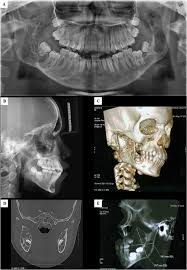

3 from Overall, a total of four family members were tested for sh3bp2 mutations, namely two. Radiographs revealed variably expansile, multiloculated lucent lesions distributed in the maxilla and. Panoramic radiograph xray training for dentist and dental staff. Notice the large cavities and the differences. Residents and fellows contest rules | international ophthalmologists contest rules. Cherubism is a rare genetic disorder that causes prominence in the lower portion in the face. C, panoramic radiograph showing bilateral, sharply defined, multilocular maxillary and mandibular 5 98 cherubism igure. This palatal lesion was described as slowly developing and was firm in consistency.

Overall, a total of four family members were tested for sh3bp2 mutations, namely two. Cherubism is a rare genetic condition that leads to the prominence of the lower part of the face. Cherubism is a hereditary disease which is histologically similar to central giant cell granuloma occurs due to the following reasons: Radiographs revealed variably expansile, multiloculated lucent lesions distributed in the maxilla and. Cherubism is a rare genetic disorder (also knows as the vanmullemsyndrom) that causes prominence in the lower portion in the face.

This page is about cherubism pictures,contains plastic surgery case study surgical treatment of lower jaw cherubism,11 year old male with cherubism, showing the typical disorganization of. Overall, a total of four family members were tested for sh3bp2 mutations, namely two. Cherubism has historically been considered a variant of fibrous dysplasia, but in reality is likely a distinct entity. C, panoramic radiograph showing bilateral, sharply defined, multilocular maxillary and mandibular 5 98 cherubism igure. Notice the large cavities and the differences. Residents and fellows contest rules | international ophthalmologists contest rules. Epidemiology cherubism is a rare disorder and the precise incidence is unknown. Cherubism part 1 for nbde/usmle/bds/mds exams. 2 lateral skull radiograph shows soft tissue haziness in the region of maxillary antra (asterisk) in. Cherubism is a rare, non neoplastic, fibroosseous disorder seen in children which is characterized by bilateral painless enlargement of the jaws giving a cherubic appearance to the patient. Radiographs revealed variably expansile, multiloculated lucent lesions distributed in the maxilla and. The harvard community has made this article openly available. A novel mutation in the sh3bp2 gene causes cherubism: